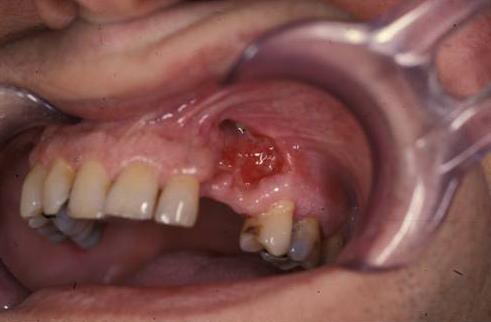

Инфецирование после удаления зуба

Одна из разновидностей болезни — остеомиелит челюсти. Он возникает при попадании инфекции контактным путем после экстракции зуба, сопровождается выраженным болевым синдромом с невозможностью выполнять жевательные функции. Проблема требует немедленного лечения, так как резко нарушается качество жизни пациента.

Поражение челюсти

Очаги хронической инфекции часто расположены в ротовой полости: плохо излеченные кариозные зубы, тонзиллиты, гаймориты приводят к попаданию микроорганизмов в область верхней или нижней челюсти. Так развивается остеомиелит, которому способствуют травмы лица, осложненные пункции гайморовых пазух или экстракции зуба. Клиника одонтогенного остеомиелита включает следующие симптомы:

• сильная боль в пораженной зоне;

• резкий отек слизистой рта и кожи над пострадавшей челюстью;

• повышение температуры;

• асимметрия лица;

• слабость, резкая утомляемость.

У больного нарушается функция жевания, так как зачастую сложно открыть рот. Меняется речь, присоединяются головные боли. Интоксикация нарастает, а процесс склонен к быстрому распространению при отсутствии помощи. Поэтому симптомы и лечение оценивает врач-стоматолог с целью принятия решения о ведении больного.

Поражение кости требует хирургической санации челюсти, которая выполняется путем открытого доступа через ротовую полость. Дальнейшая тактика — иммобилизация шиной с последующим рентгенологическим контролем за изменениями в костной ткани. Назначается консервативная терапия антибиотиками с расширенным спектром действия. Особенно часто используются Метронидазол в сочетании с цефалоспоринами 3-4 поколений. Дополнительно назначаются фторхинолоны или Рифампицин. Можно помочь больному и народными средствами. Для этого используется полоскание фито-антисептиками, которые входят в состав ромашки, календулы или эвкалипта. Состав можно приготовить самостоятельно, но предпочтительнее использовать в разведении готовые аптечные настойки этих растений.

Остеомиелит в стоматологии

Поражение челюстей играет ведущую роль в генезе остеомиелита после экстракции зубов. Заражение происходит в стоматологическом кабинете или дома вследствие неправильного ухода за послеоперационной раной. Основные симптомы связаны с поражением ротовой полости: